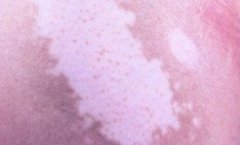

白癜风为什么会久治不愈?白癜风的特点就是易诊断,难治愈。很多白癜风患者都为此烦恼不已,都像知道白癜风为什么会久治不愈。

白癜风为什么会久治不愈呢?成都白癜风医院医生为您分析了三点原因,希望对患者有所帮助。